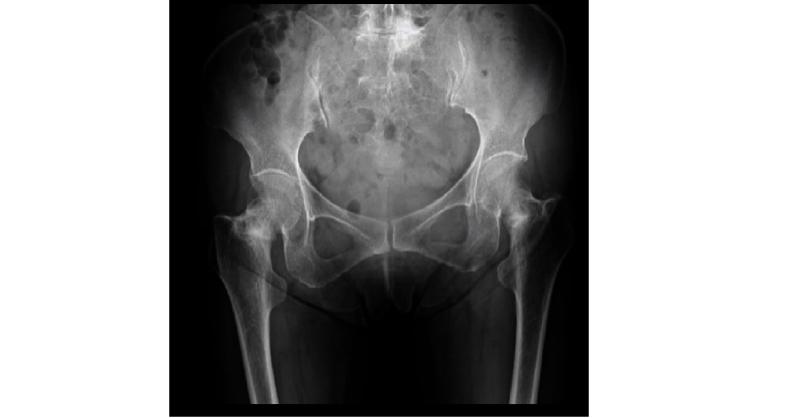

A 74-year-old woman with no history of surgery or fractures in the lower extremities and with no other medical history reported co-occurrence of pain on both sides of the hip. Although she had no habit of taking walks, she had started walking for 30 min daily for 5 months for her health before the appearance of pain. She was diagnosed with bilatera